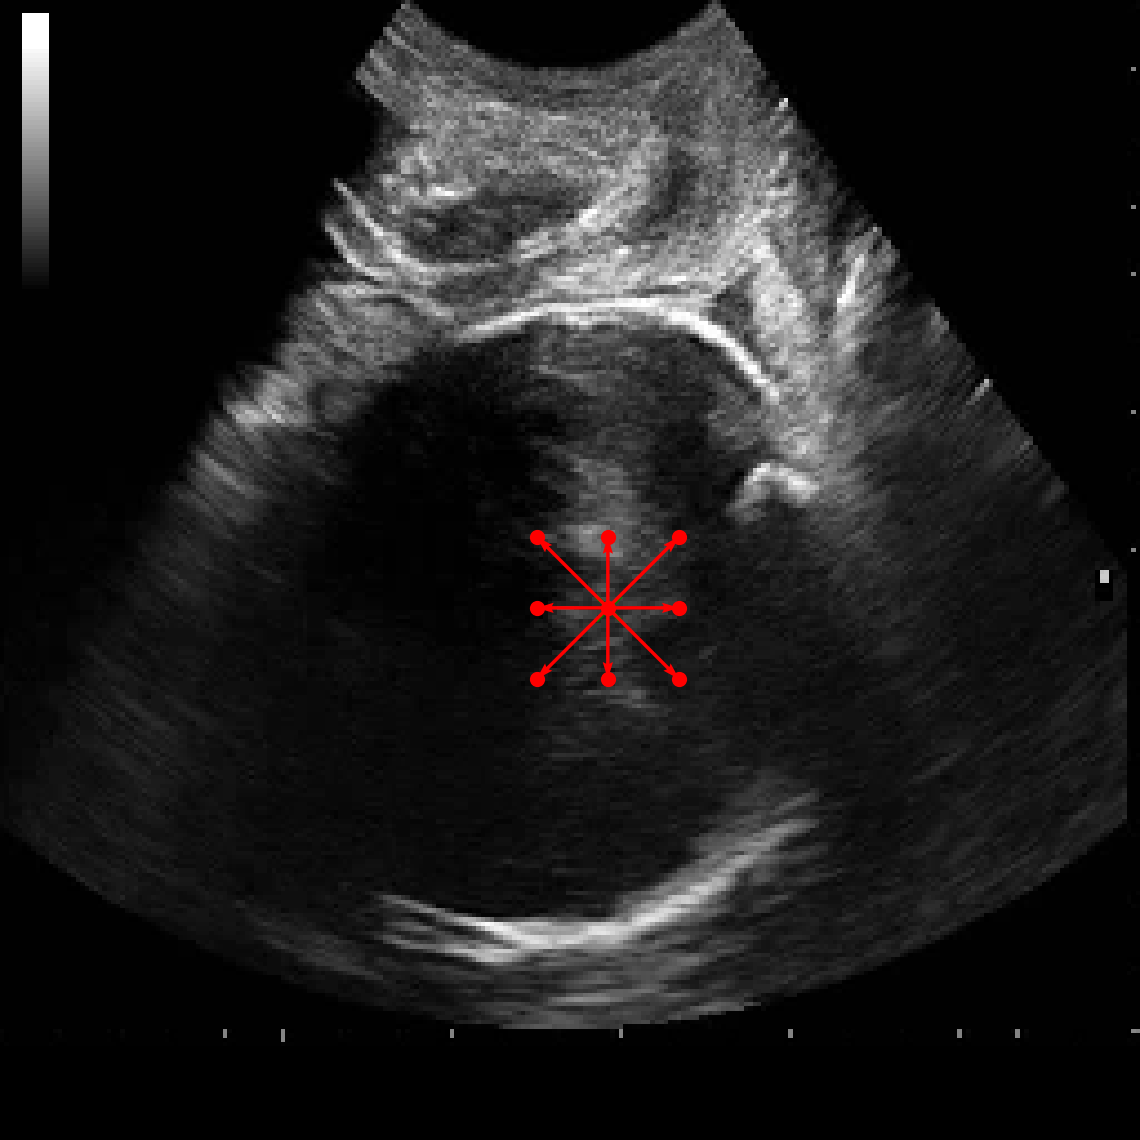

In practical clinical settings, medical images are often incomplete or degraded due to occlusions, artifacts, or limited fields-of-view. Therefore, a reliable segmentation model must be robust to missing spatial context and capable of inferring anatomical structures from partially observed inputs. To evaluate this critical property, we conducted a masking experiment using the FH-PS-AoP dataset. In this experiment, we systematically removed one quadrant from the input image, top-left, top-right, bottom-left, or bottom-right, and evaluated the performance of DAUNet compared to the baseline UNet.

Figure 7 presents a comprehensive visual comparison of the predicted offset maps and segmentation masks under each masking condition. The first column shows the original (unmasked) input along with its corresponding predictions, while subsequent columns depict the results for each of the masked quadrants.

DAUNet demonstrates markedly higher resilience to missing context compared to UNet. Its predicted offset maps remain dense and structured, with vectors that preserve anatomical directionality even when significant regions of the input are absent. This behavior reflects DAUNet’s ability to infer context from the remaining visual cues. In contrast, UNet exhibits sparse or disoriented offsets in the masked scenarios, indicating reduced spatial awareness and compromised localization.

To better understand this phenomenon, we analyzed the receptive fields of both models. For a representative pixel, we visualized its corresponding receptive area contributing to the output. In UNet, the receptive field is fixed and grid-constrained (refer to second row of Figure 7), making it sensitive to occlusions. On the other hand, DAUNet leverages deformable convolutions to dynamically adjust its receptive field based on the visible content. This adaptability is evident in the red and white arrows in the fourth column of Figure 7, where DAUNet modifies its offset patterns to account for the masked input.

The segmentation masks in third and fourth rows of Figure 7, further substantiate these findings. DAUNet consistently produces anatomically plausible segmentations of both the fetal head (green) and pubic symphysis (red), with minimal degradation even under 25% missing input. The output contours remain smooth, accurate, and well-aligned with ground truth boundaries. In contrast, UNet’s performance deteriorates noticeably, with fragmented or distorted segmentations, especially around the fetal head, as indicated by white arrows in the figure.

These results highlight the efficacy of DAUNet’s architectural innovations. The combination of deformable convolution and SimAM attention allows the model to effectively reason over the visible context and compensate for spatial omissions. This robustness to incomplete inputs makes DAUNet well-suited for deployment in real-world medical environments, where noise, occlusions, and partial data are common challenges.